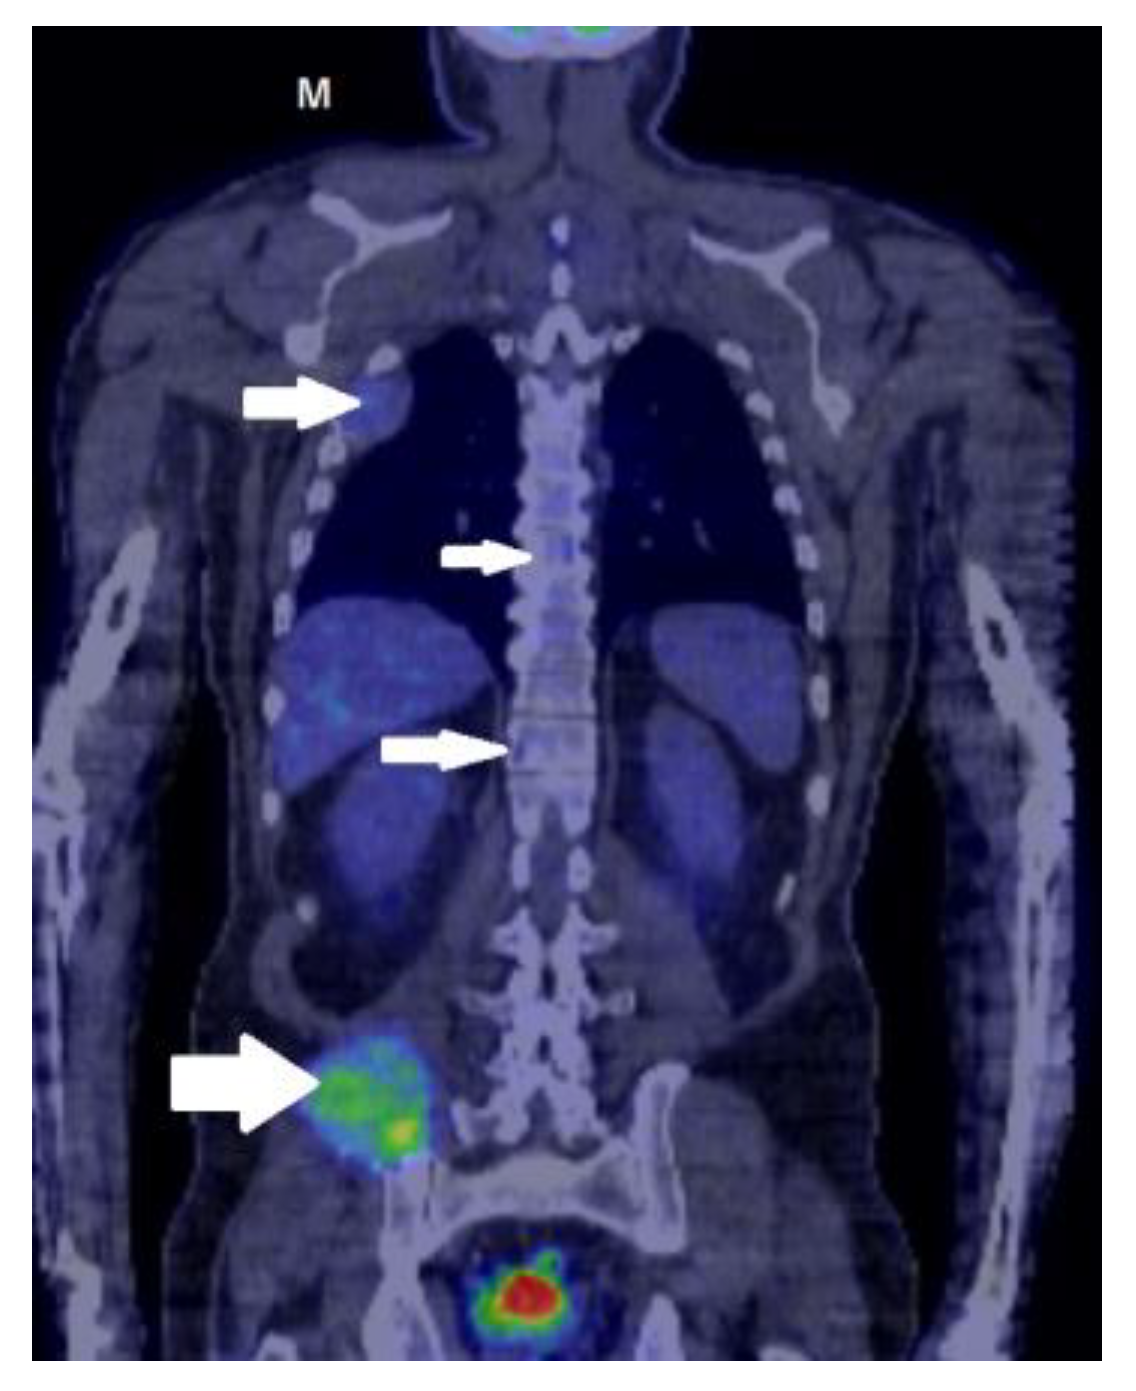

2. Case Report